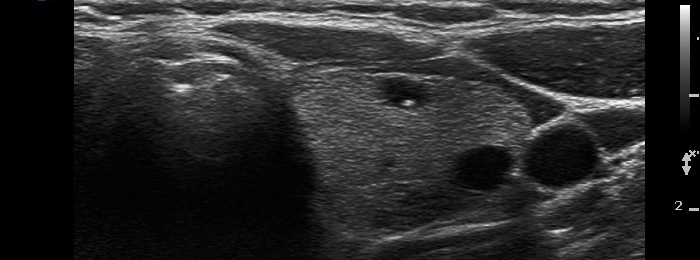

There are numerous hyperechogenic granules in the lower pole of the nodule. These figures might be confused with punctate echogenic foci (microcalcifications), as happened in this case. However, several have dorsal tail and therefore the remaining without a tail likely belong also to the same subgroup.